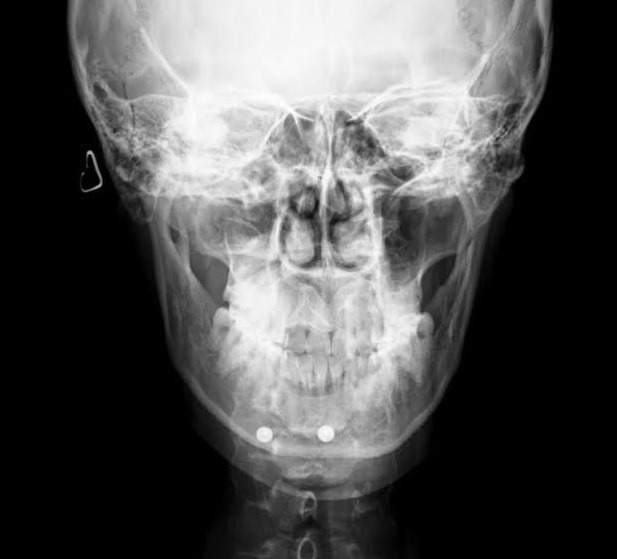

正面視では下口唇からオトガイ先端までの距離が長く、

フェイスラインも比較的細いため、

中央を大きめに切除し、

やや発達気味の左側を大きめで切除します。

今回もオトガイ神経を切断することなく、

手術を終えることができました。